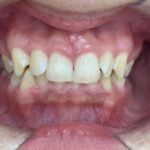

Before Braces - 治療前 -

犬歯と第一大臼歯のⅡ級関係が見られます。

また、前歯に過度なジェットが見られます。